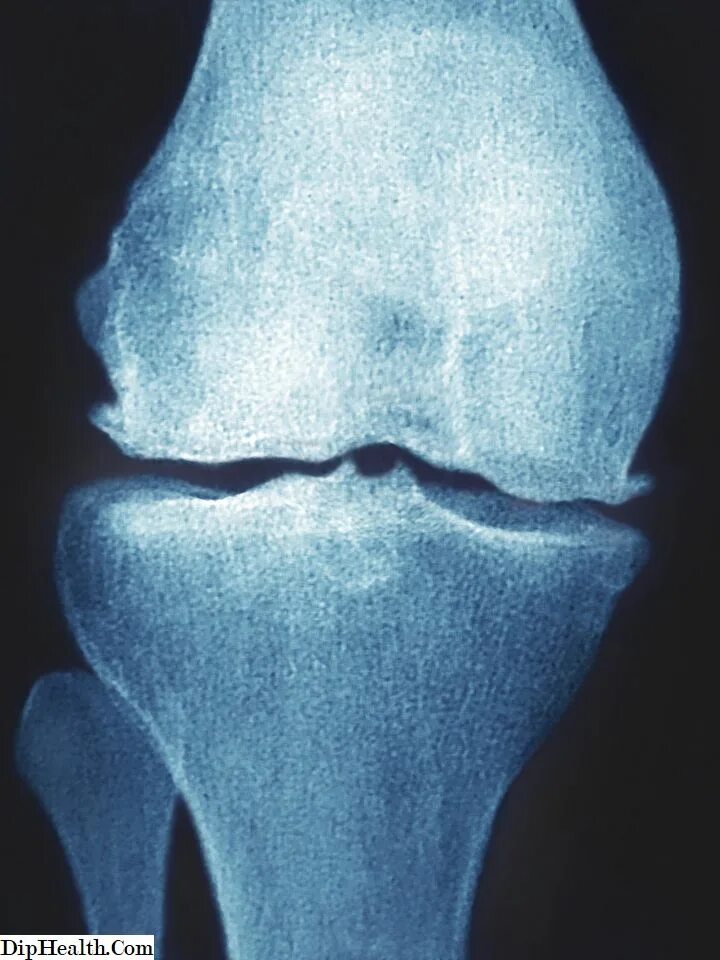

Остеофит симптомы